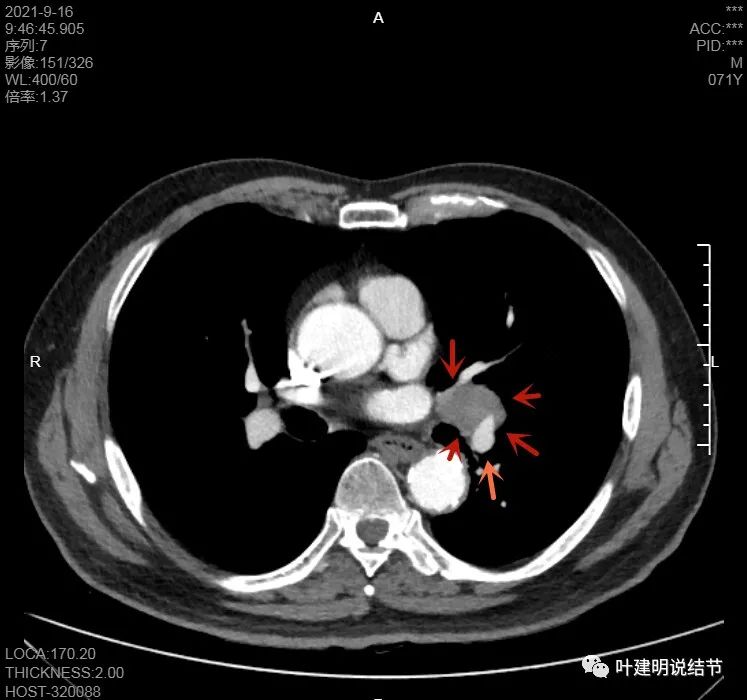

上图示病灶在左下叶,红色所指的与绿色箭头所指的是两个病灶,不相连的,实性结节

上图也示病灶是两个的,小的与大的之间有间隙的。大的病灶呈长方形似的

上图见主病灶长方形,边缘平直且光滑,没有毛刺、分叶或胸膜牵拉,粉色箭头示小病灶,在主病灶边上